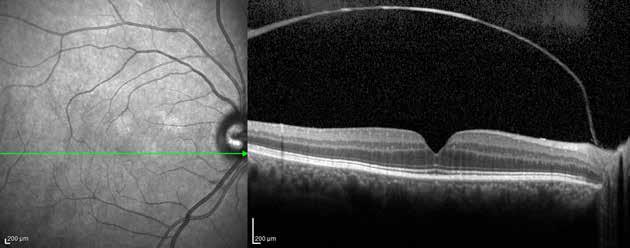

Type 3 MNV refers to the growth of vessels from the retinal circulation toward the outer retina. It is believed that vascular proliferation begins in the deep retinal capillary plexus, with the growth vector extending toward the outer retina. On FA and ICGA, Type 3 MNV appears as a hyperfluorescent intraretinal vascular complex with leakage in the late phases of the examination. Late-phase leakage ion ICGA is a unique feature of MNV lesions. Since these lesions originate from the retinal circulation, they never arise within the foveal avascular zone. Instead, they develop near its edge or at a variable distance from it, typically from the terminal portions of third-order arterioles and venules.5 (Figure 3)

Figure 3. Two examples of Type 3 macular neovascularization. In the first case, Indocyanine green angiography (B) and fluorescein angiography revealing the Type 3 macular neovascularization (arrowhead). Optical coherence tomography (C) showing the detachment of retinal pigment epithelium with the hyperreflective material related to the neovascularization. In the second case, optical coherence tomography (E) showing the intraretinal hyperreflective material related to the neovascularization with intraretinal fluid. Fundus autofluorescence (F) showing abnormalities of retinal pigment epithelium. Optical coherence tomography angiography (G) showing the neovascular lesion.